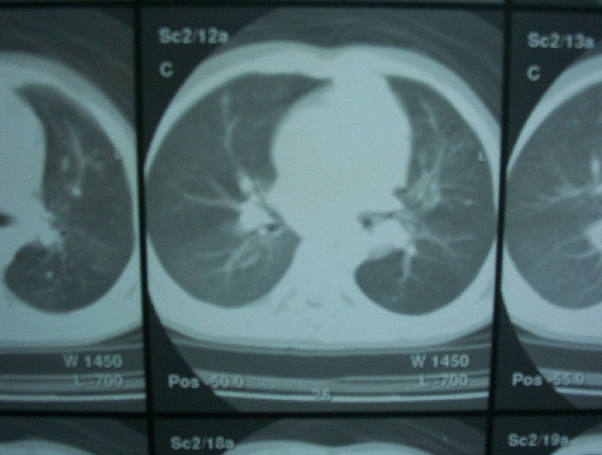

Fig 2: Chest CT scan showing bilateral mediastinal lymphadenopathy.